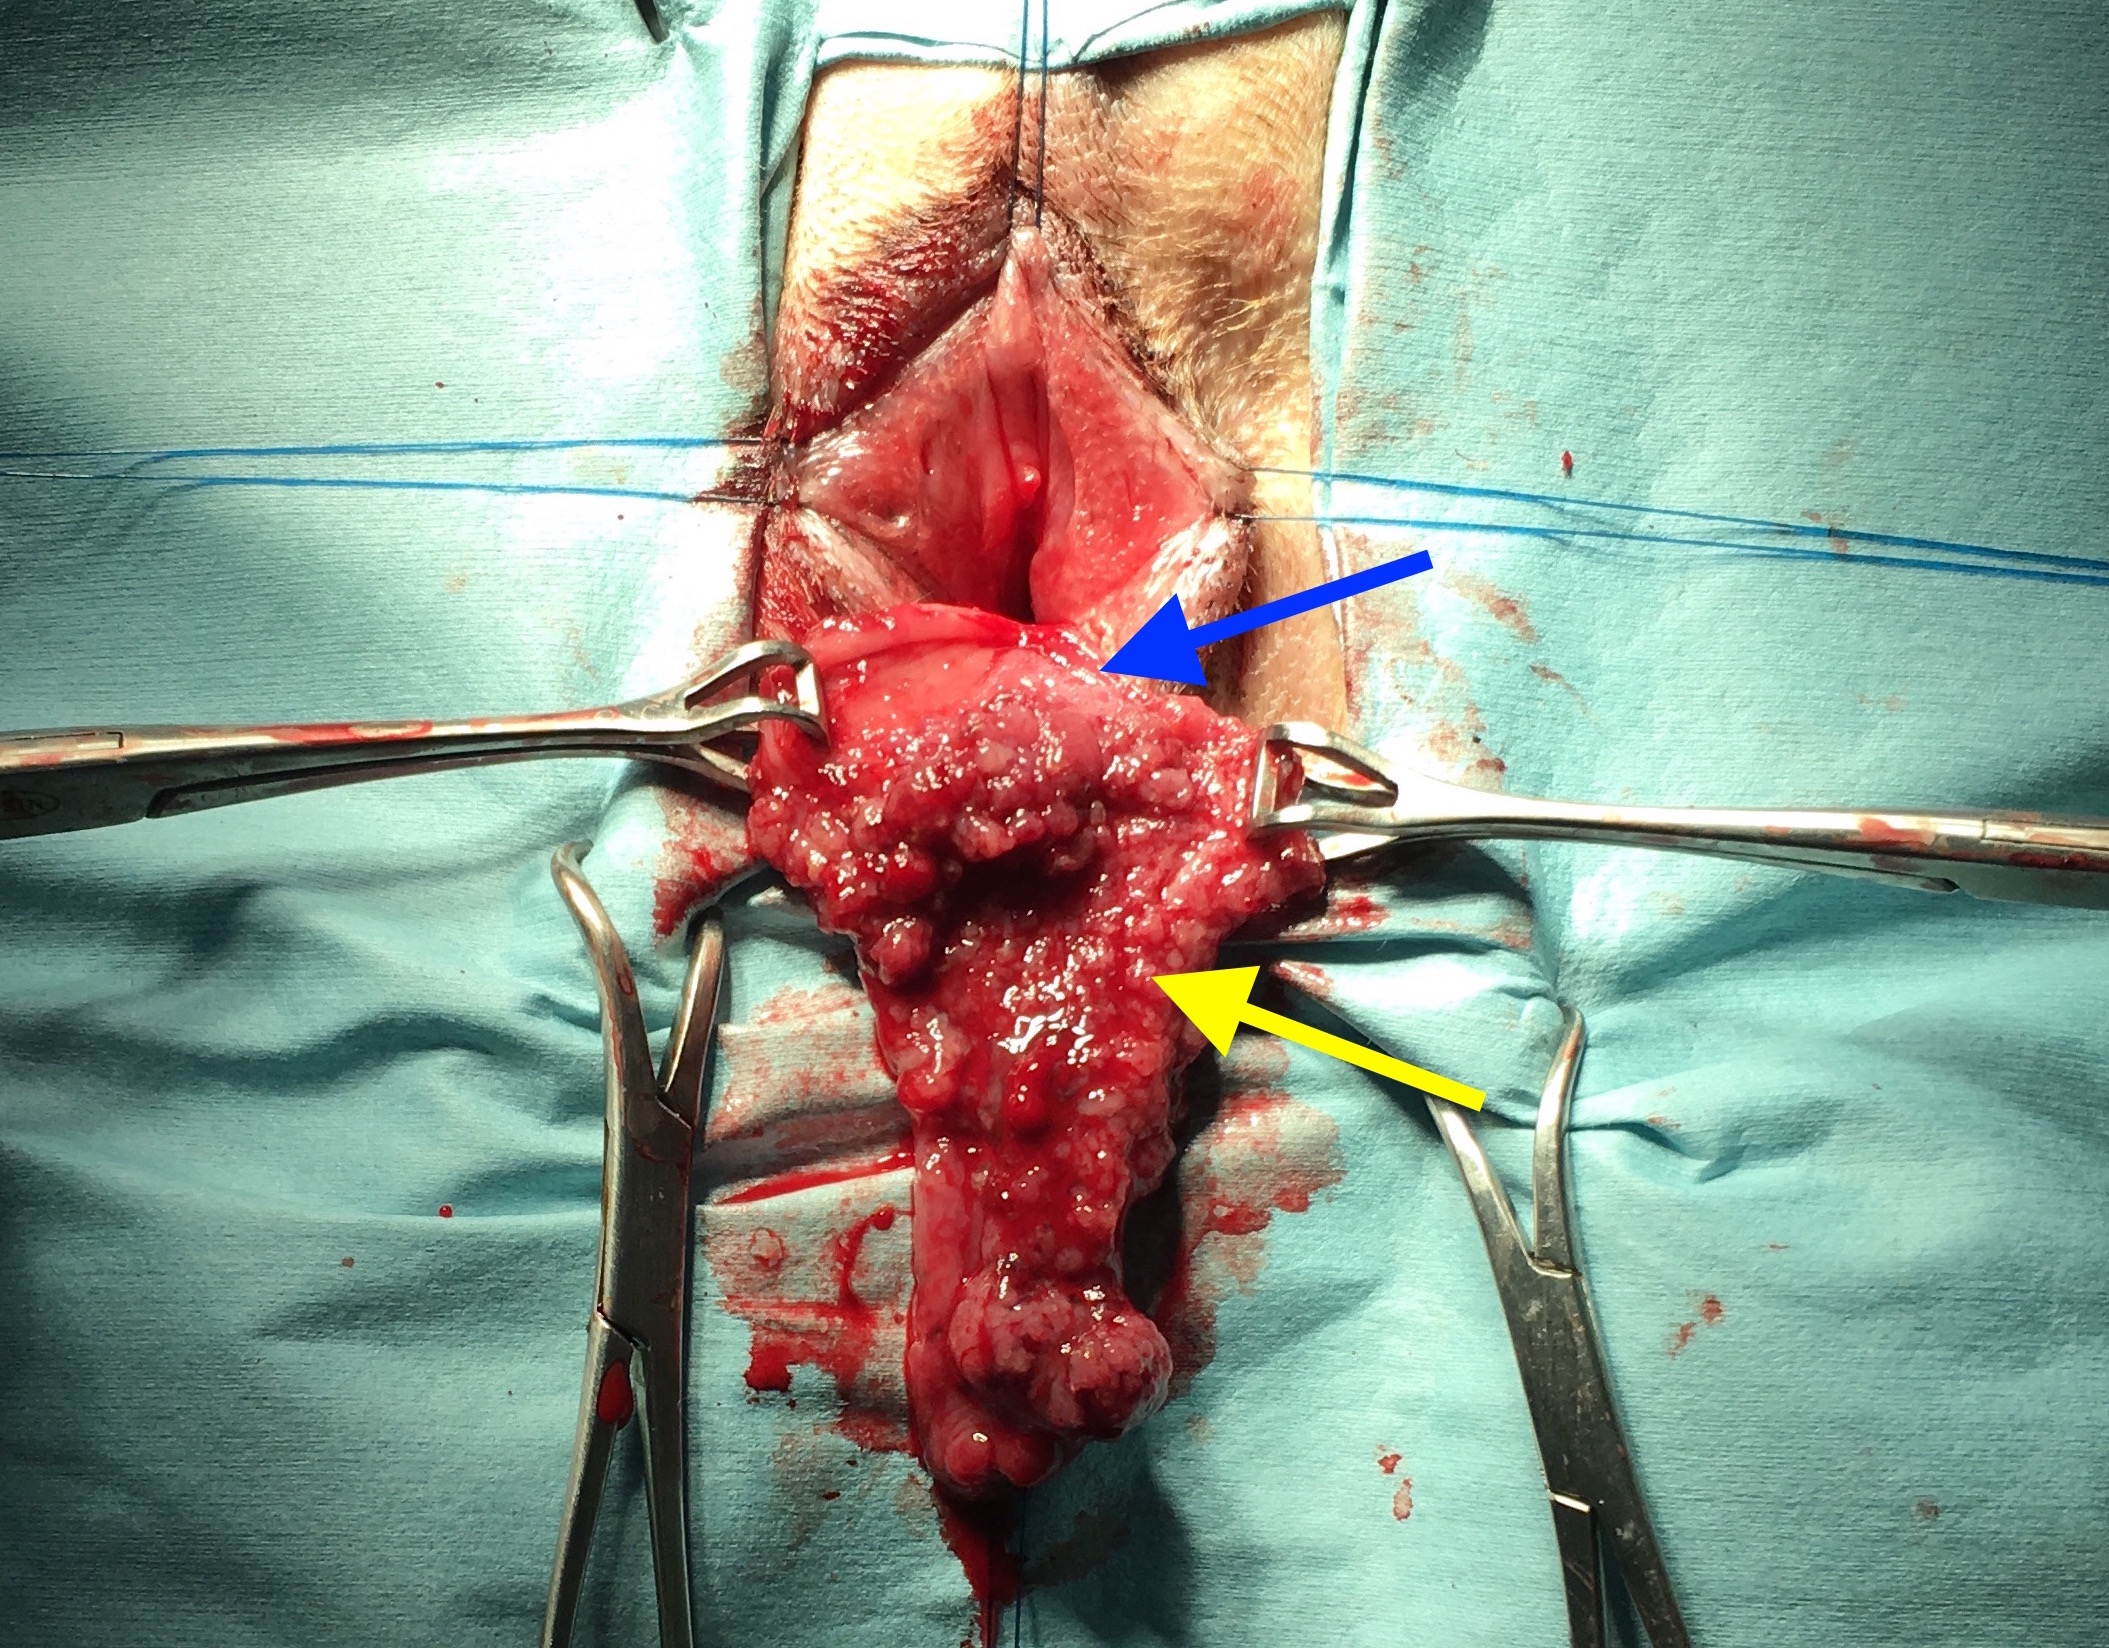

画像・写真|『週刊プレイボーイ』38号表紙(c)yorokobi/週刊プレイボーイ 2枚目 / 南里美希、シースルーまといセクシーグラビア 大人の色気直腸プルスルー法を用いて直腸切除術を行いました。 肛門から直腸を引き抜いてきて切除する術式です。 ①まずは、肛門から直腸粘膜を引きずり出します。 病変の広がりを把握するため、肛門から15cm程度離れた病変のない部位を切開します。 ②切開し 元気可愛いプルスルーブレイドアレンジ♪6 サイド&バックスタイル 画像女の子のママさん必見! 元気可愛いプルスルーブレイドアレンジ♪7 アクティブ可愛い髪型でしたよね♪ 手が込んでいる分、とっても豪華ですね! 子供も喜ぶこと

![]() 犬の大腸癌の手術法 新千歳動物病院のブログ | ![]() 犬の大腸癌の手術法 新千歳動物病院のブログ | ![]() 犬の大腸癌の手術法 新千歳動物病院のブログ |

犬の大腸癌の手術法 新千歳動物病院のブログ | 犬の大腸癌の手術法 新千歳動物病院のブログ | ![]() 犬の大腸癌の手術法 新千歳動物病院のブログ |

犬の大腸癌の手術法 新千歳動物病院のブログ | ![]() 犬の大腸癌の手術法 新千歳動物病院のブログ | ![]() 犬の大腸癌の手術法 新千歳動物病院のブログ |